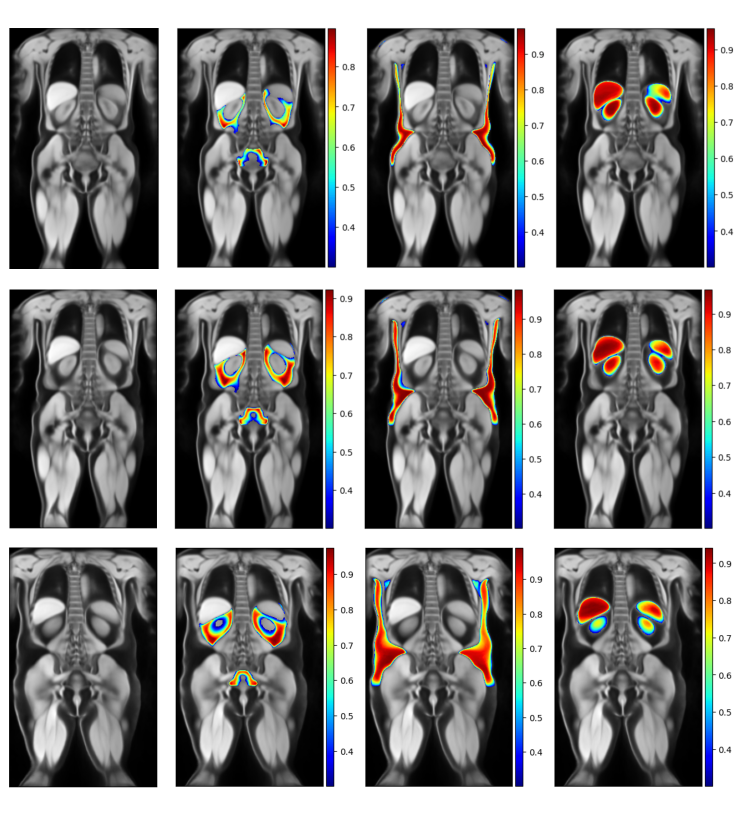

Female Atlases

Figure 7 shows example slices of the female atlases for each category. The figure shows the water-contrast anatomical atlas side by side with the visceral fat label atlas, the subcutaneous fat label atlas, and the abdominal organs label atlas. Each row corresponds to a different BMI group, from normal (first row) to overweight (middle row) to obese (final row). The colour bar represents the probability of the labels.

Refer to caption

Figure 7: Overview of the female atlases for the healthy (first row), overweight (middle row) and obese (last row) groups.